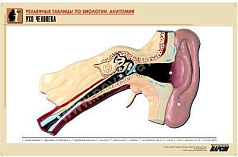

Комплект включает в себя 21 таблицу следующего содержания:

7. Ухо человека;